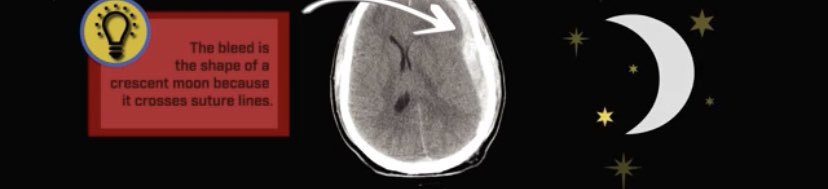

▫️Subdural hematoma🩸🧠

✳️Cresent shape that cross suture lines

✳️Have 3 main types 🌟👇🏻

🛑notice that, the acute commenly have medline shift